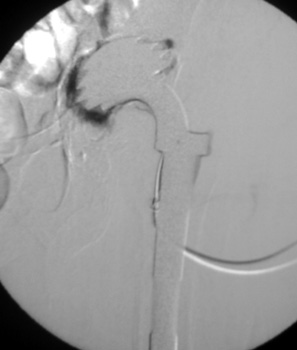

Arthrographic evidence of cup looseningcontrast enters

abnormally widened interface Gruen zone II and III